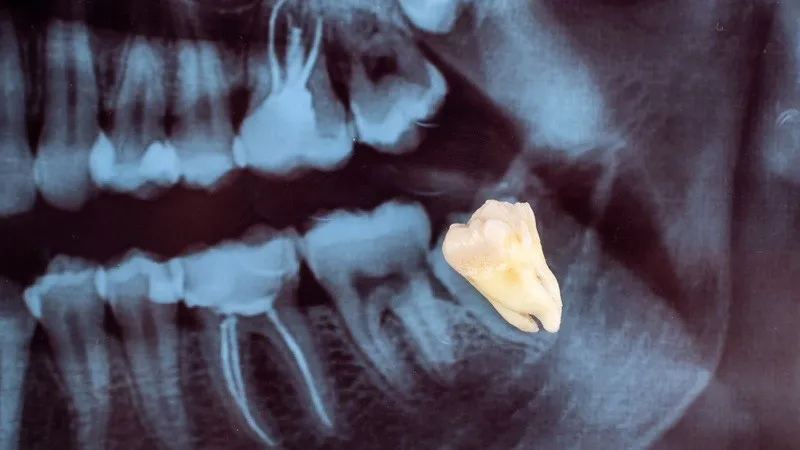

Răng mọc ngầm trong xương là tình trạng thường gặp, đặc biệt ở răng khôn, gây ra nhiều biến chứng như đau nhức, viêm nhiễm, thậm chí